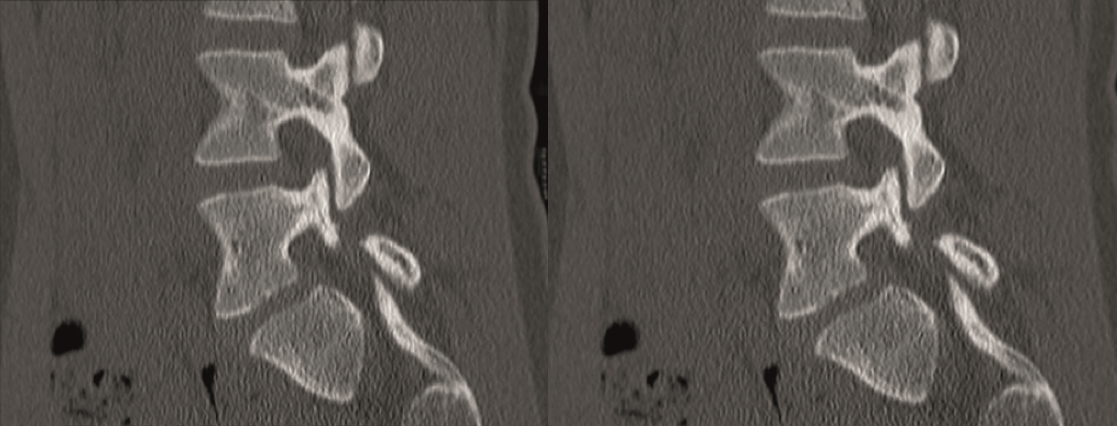

A CT scan allowed a more detailed assessment (Fig 7). There was an obvious nonunion at L5/S1, with loose screws in the sacrum (red circle). Furthermore, there was instability at L4/L5 as the intervertebral disc presented with an important vacuum phenomenon (asterisk). Foraminal stenosis at L5/S1 (not shown) seemed to be the reason behind the persistent leg pain.